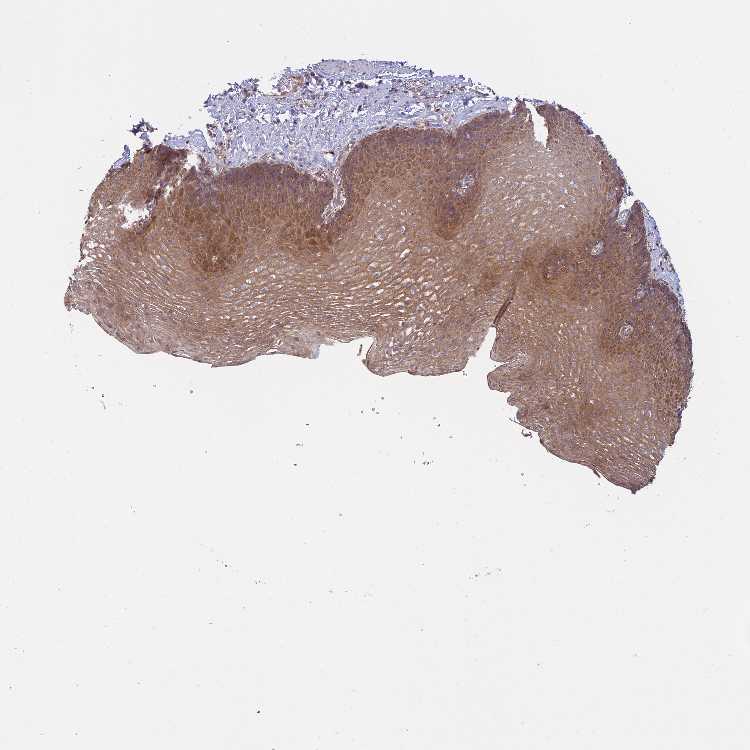

ESOPHAGUS - Antibody stainingi

Antibody staining in the annotated cell types in the current human tissue is reported as not detected, low, medium, or high, based on conventional immunohistochemistry profiling in selected tissues. This score is based on the combination of the staining intensity and fraction of stained cells.

Each image is clickable and will lead to virtual microscopy that enables deeper exploration of all samples and also displays staining intensity scores, fraction scores and subcellular localization as well as patient and tissue information for each sample.

Antibody HPA002912

Squamous epithelial cells Medium